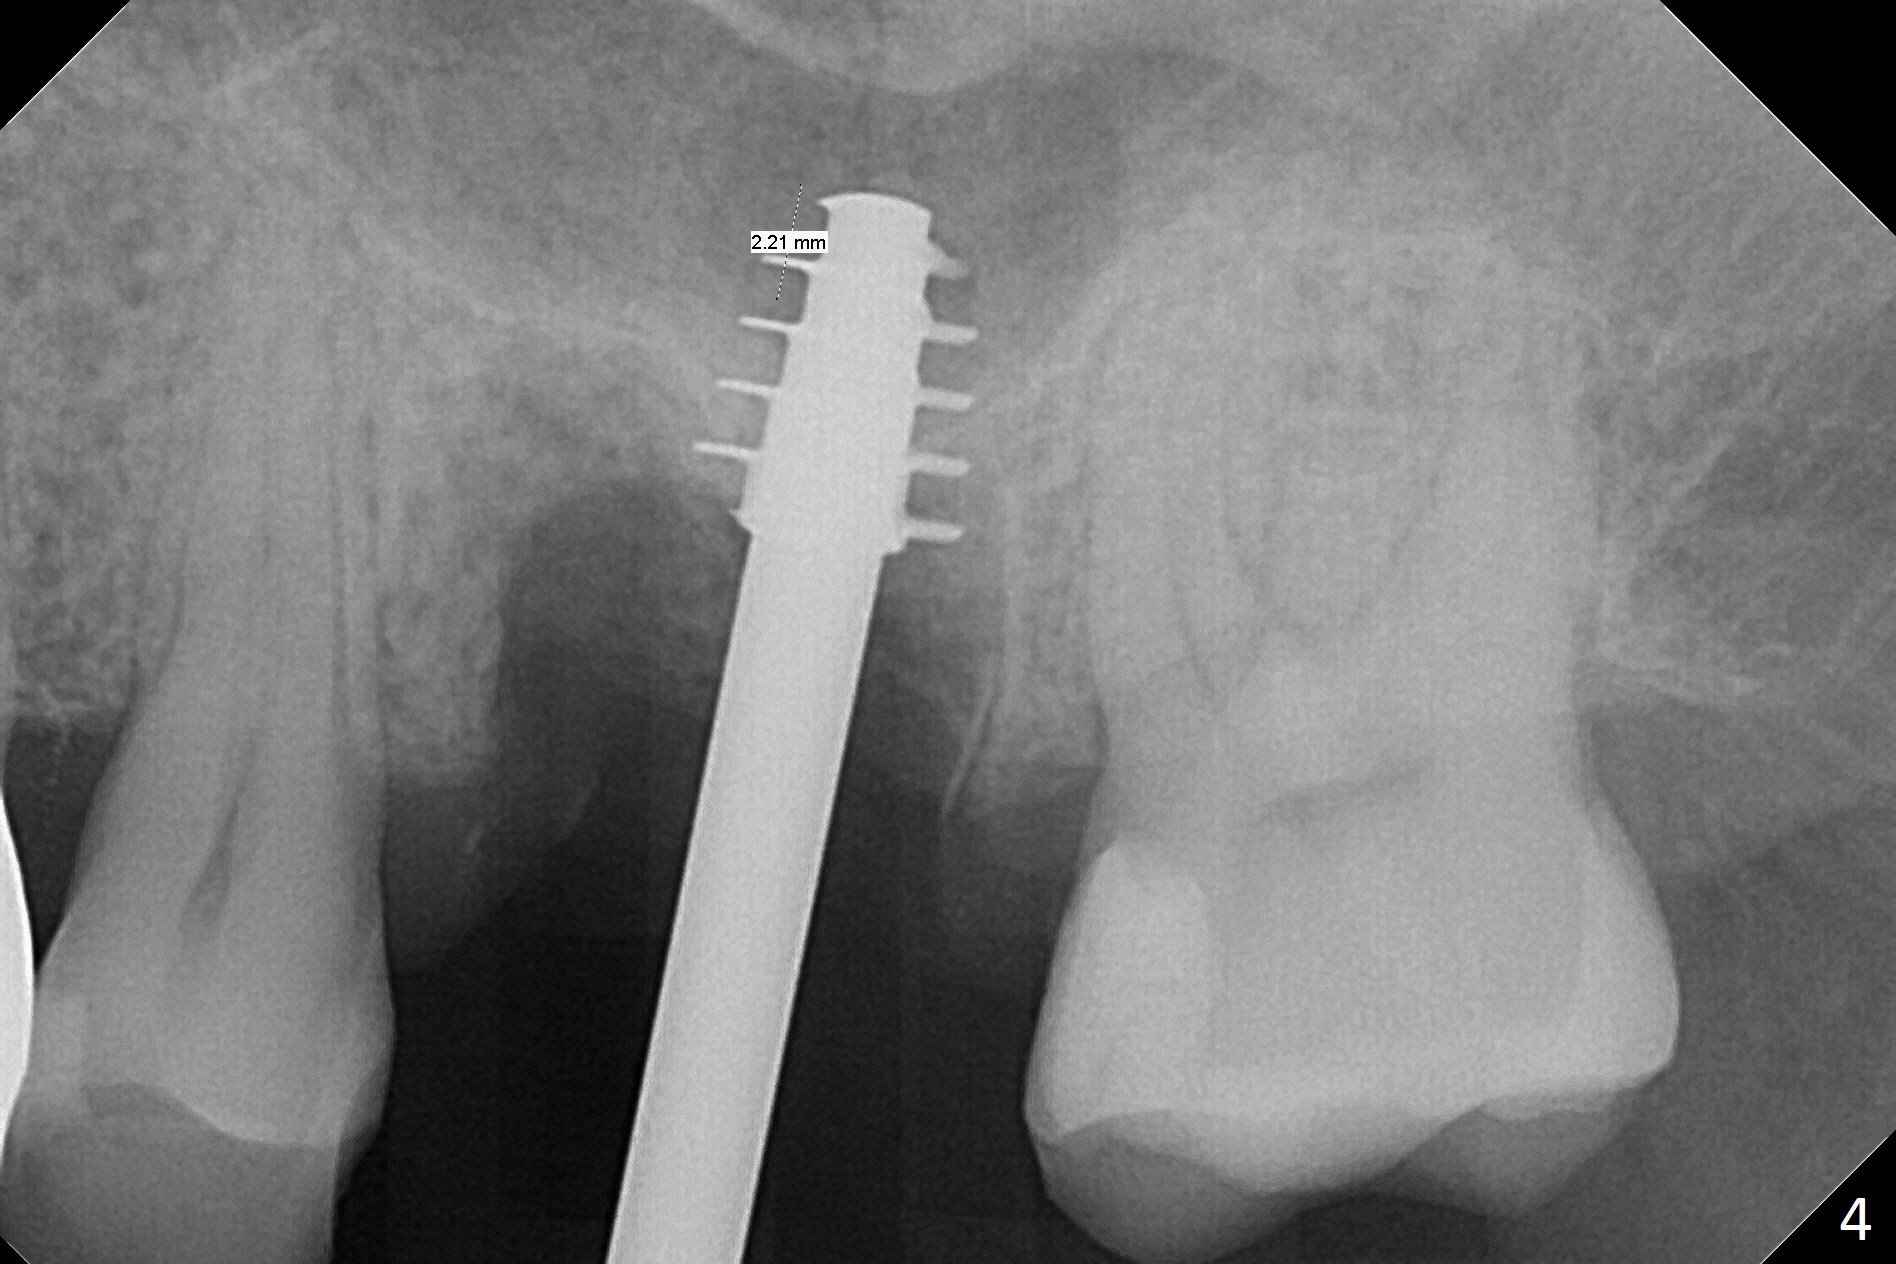

What is unclear preop is the large periapical radiolucency (Fig.1 red dashed line) of the palatal root (P) of the tooth #14.  When the tooth is extracted, it is difficult to remove granulation tissue from the palatal apical socket, which is enlarged (Fig.2 (impression of sockets),3).   The small dimension of the septum (~4x5 mm (Fig.1 pink) is also unrecognized preop, which leads to sinus perforation when 4.8 mm Magic Drill is used.  In spite of use of PRF plug and membrane, allograft does not stay in the osteotomy after placement of 4x11 mm dummy implant or 5 mm tap drill (Fig.4 for 9 mm).  Finally a 5.5x7 mm IBS implant is placed with 30 Ncm (Fig.5).  After placement of Osteogen plug in the apical portion of the sockets, allograft/Osteogen is placed in the remaining sockets (Fig. 5 *).  The latter is partially contained by a 6.5x4(3) mm abutment (A) and ultimately by an immediate provisional.

To avoid sinus membrane perforation, the initial osteotomy should be coronal to the sinus floor by 1 mm.